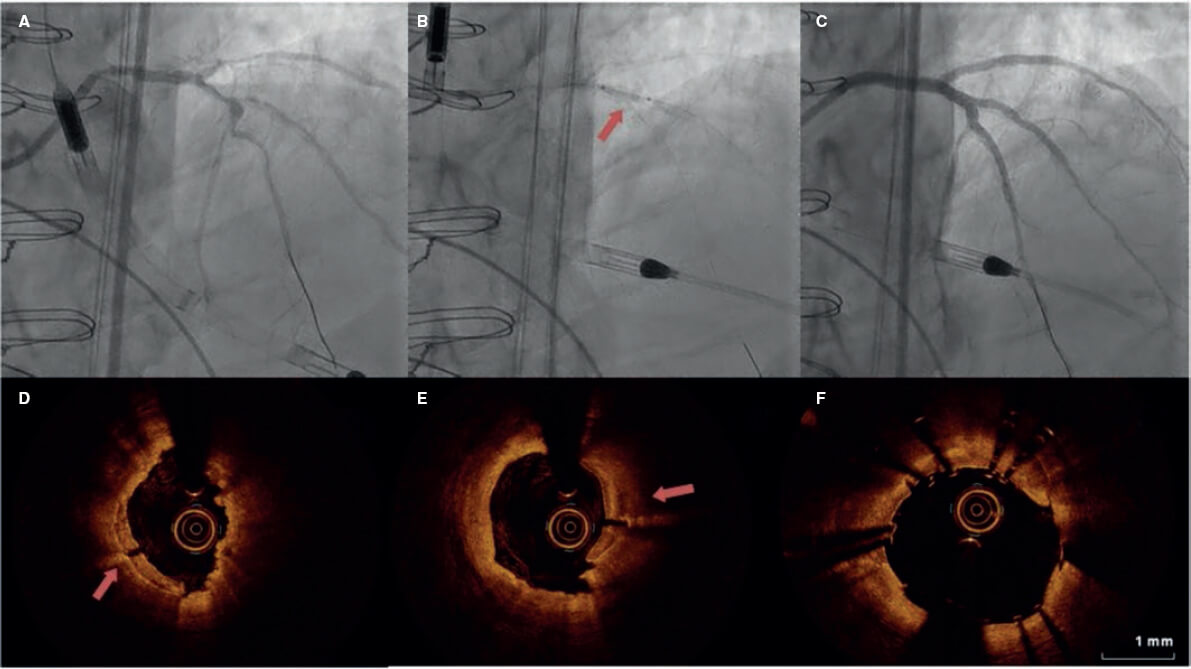

Respecto a la intervención, se debe mencionar que la capacidad de cruce de la lesión del balón de LIC fue del 100%, si bien en la mayoría de pacientes se realizó una técnica de preparación de la placa previo a la LIC (el 62% con predilatación con balón y el 27% con aterectomía rotacional). Recientemente, la combinación aterectomía rotacional/LIC, descrita como RotaTripsy, ha sugerido que ambas técnicas de debulking se complementan ya que la aterectomía rotacional permite cruzar el balón de LIC y esta última facilita una correcta expansión en presencia de placas circunferenciales profundas de calcio9. El índice de éxito del dispositivo fue del 84% (100% en el estudio Disrupt CAD II) y el índice de éxito clínico del 95% (94% en el estudio Disrupt CAD II). Y, lo más importante, no hubo complicaciones importantes asociadas a la intervención en consonancia con lo descrito en los resultados del Disrupt CAD II. La rotura del balón de LIC durante el inflado sobrevino en 3 casos (12%) sin complicaciones asociadas, si bien recientemente se ha descrito un caso de rotura del balón que resultó en una disección coronaria tipo C, por lo que el cardiólogo intervencionista debe estar atento a esta posible complicación asociada a la litotricia10. Fueron pocos los casos en los que se obtuvieron imágenes intravasculares, probablemente porque el operador pensó que sería difícil cruzar una lesión especialmente grave y calcificada con el catéter de la OCT o IVUS. En consonancia con lo descrito por los estudios Disrupt CAD I y II y el substudio OCT5,11, se confirmó que tanto la modificación del calcio como la presencia de fracturas acarreó una ganancia de área aguda y una favorable expansión del stent en las lesiones estudiadas mediante OCT en nuestra serie. La figura 1 muestra la angiografía coronaria y OCT de un paciente complejo tratado con LIC; las flechas rojas de la figura 1D-E indican fracturas de calcio después de realizar la LIC.

Figura 1. Litotricia intracoronaria, angiografía y tomografía de coherencia óptica. Paciente con enfermedad coronaria grave y fracción de eyección del ventrículo izquierdo gravemente deprimida tratado previamente mediante cirugía de revascularización coronaria (injerto venoso en descendente anterior izquierda, ocluido en la actualidad). Tratamiento de tronco común, descendente anterior izquierda y ramas diagonales. A: angiografía previa a litotricia intracoronaria. B: ICP asistida por el dispositivo Impella de descendente anterior izquierda. La flecha indica el balón de litotricia inflado. C: resultado angiográfico final exitoso tras implante del stent. D, E y F: imágenes de la tomografía de coherencia óptica de una lesión calcificada postlitotricia. Las flechas rojas indican microfracturas de calcio tras la litotricia intracoronaria.